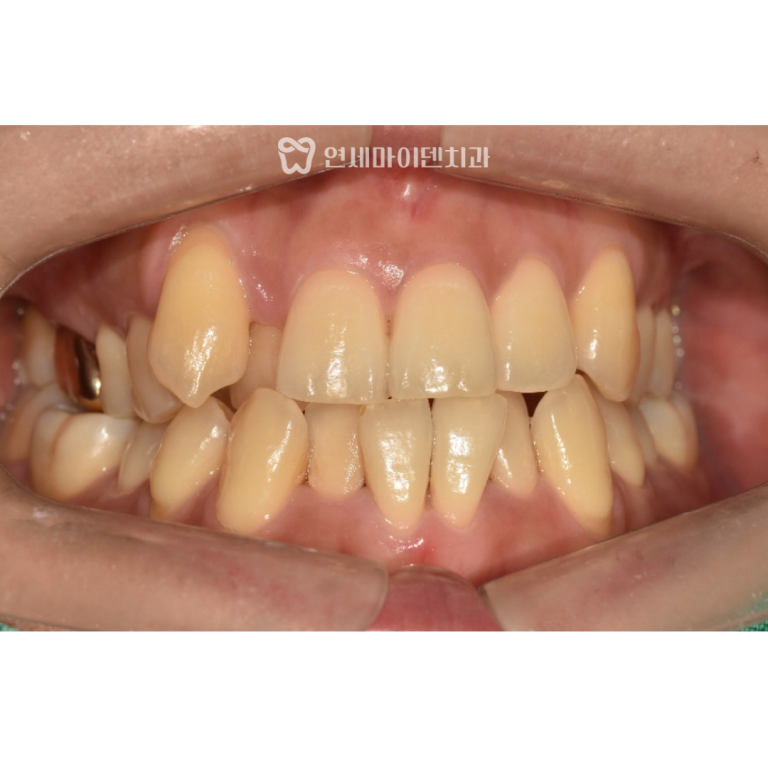

환자분은 과거에 시술받은 임플란트 중

일부 보철물이 파절된 상태였습니다.

하지만 다행히 임플란트 본체는 건강하게 유지되고 있었습니다.

이에 따라 기존 임플란트는 그대로 두고,

상부 보철물만 새로 제작했습니다.

이번에는 교합면 방향과 잇몸 형태를 고려하여

맞춤형 지대주(abutment)를 적용했습니다.

이는 향후 파절 위험을 줄이고

심미적 완성도를 높이는 데 도움이 됩니다.